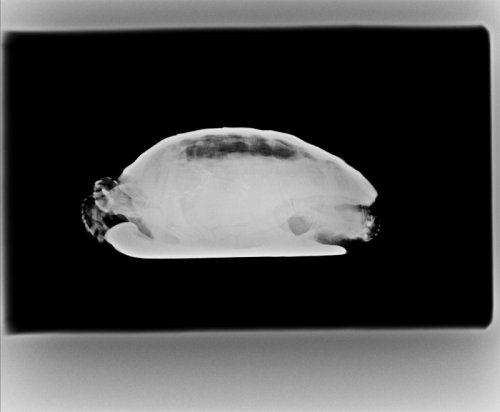

Герпетологов у нас мало, если и есть хороший, то недобратся далеко от дома, я сам тяжело болен, еле встаю с кровати. Связался с ближайшим герпетологом, принял лишь через три дня, только взглянул и сразу высказался, что лечение ничем не поможет. Потом сделал рентген, обсудили рентгенограмму, что лёгкие отекли. Анализы крови сделать не смогли, ибо они отправляют их в Германию, что очень дорого. Дальше проводим такие диалоги уже несколько дней:

Приложу рентгенограммы и фотографии 3-дневной давности.

У Вас нет проекции рентгена, которая бы точно показывала отёк легких или воспаление. Для этого делают кранио-каудальную, а боковую как вспомогательную. Нагревательные коврики запрещены к использованию у черепах. Они плохо чувствуют температуру пластроном, она не может контролировать прогрев на нём, он греет только ближайшие органы, что вредно для черепахи. Я не собираюсь Вам на каждое своё предложение приводить научные статьи и ссылки на ветеринарные статьи, у меня времени на это столько нет и желания что-либо Вам доказывать, потому что Вы не выглядите как человек которому нужна помощь. Я Вам говорю что делать - Вы пререкаетесь и пытаетесь меня убедить, что это не так. Ну не так - ищите там где будет так.

Рентген с боку, черная полоса это лёгкие, их размер 3 раза меньше чем неотекших лёгких.

По рентгену сильная компрессия лёгких, но это не жидкость в них. Легкие это как раз та маленькая светлая область, а затемнение это то, что на них давит - жкт, возможно фолликулы. Черепахе нужны анализ крови, уколы кальция и витаминов, купание и да, вибротерапия, чтобы избавиться от застоя, который давит на лёгкие.

Все препараты нужно колоть в переднюю часть из-за сильных отёков. Прогноз неблагоприятный при отсутствии очного осмотра у адекватного герпетолога, т.к. если это фолликулы, то поможет только операция.

Антибиотики и мочегонное её добьют. Дальше Вам решать что делать с этой информацией.